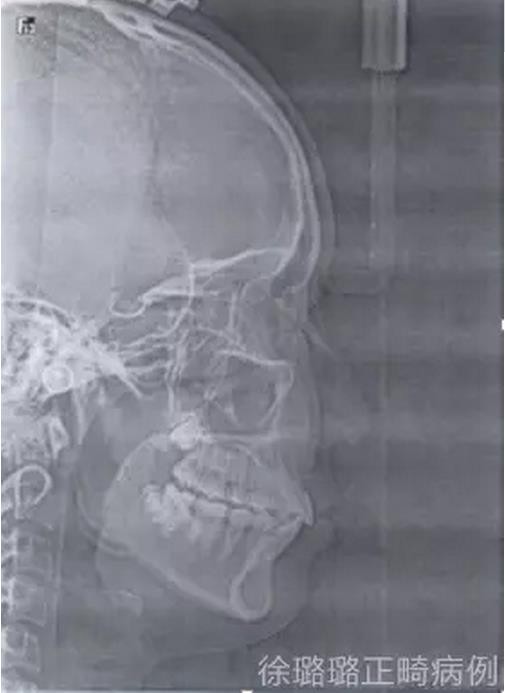

影像學(xué)檢查

X 線檢查:替牙列,上頜雙側(cè)尖牙埋伏阻生(含牙囊腫),四顆第三恒磨牙牙胚存在。